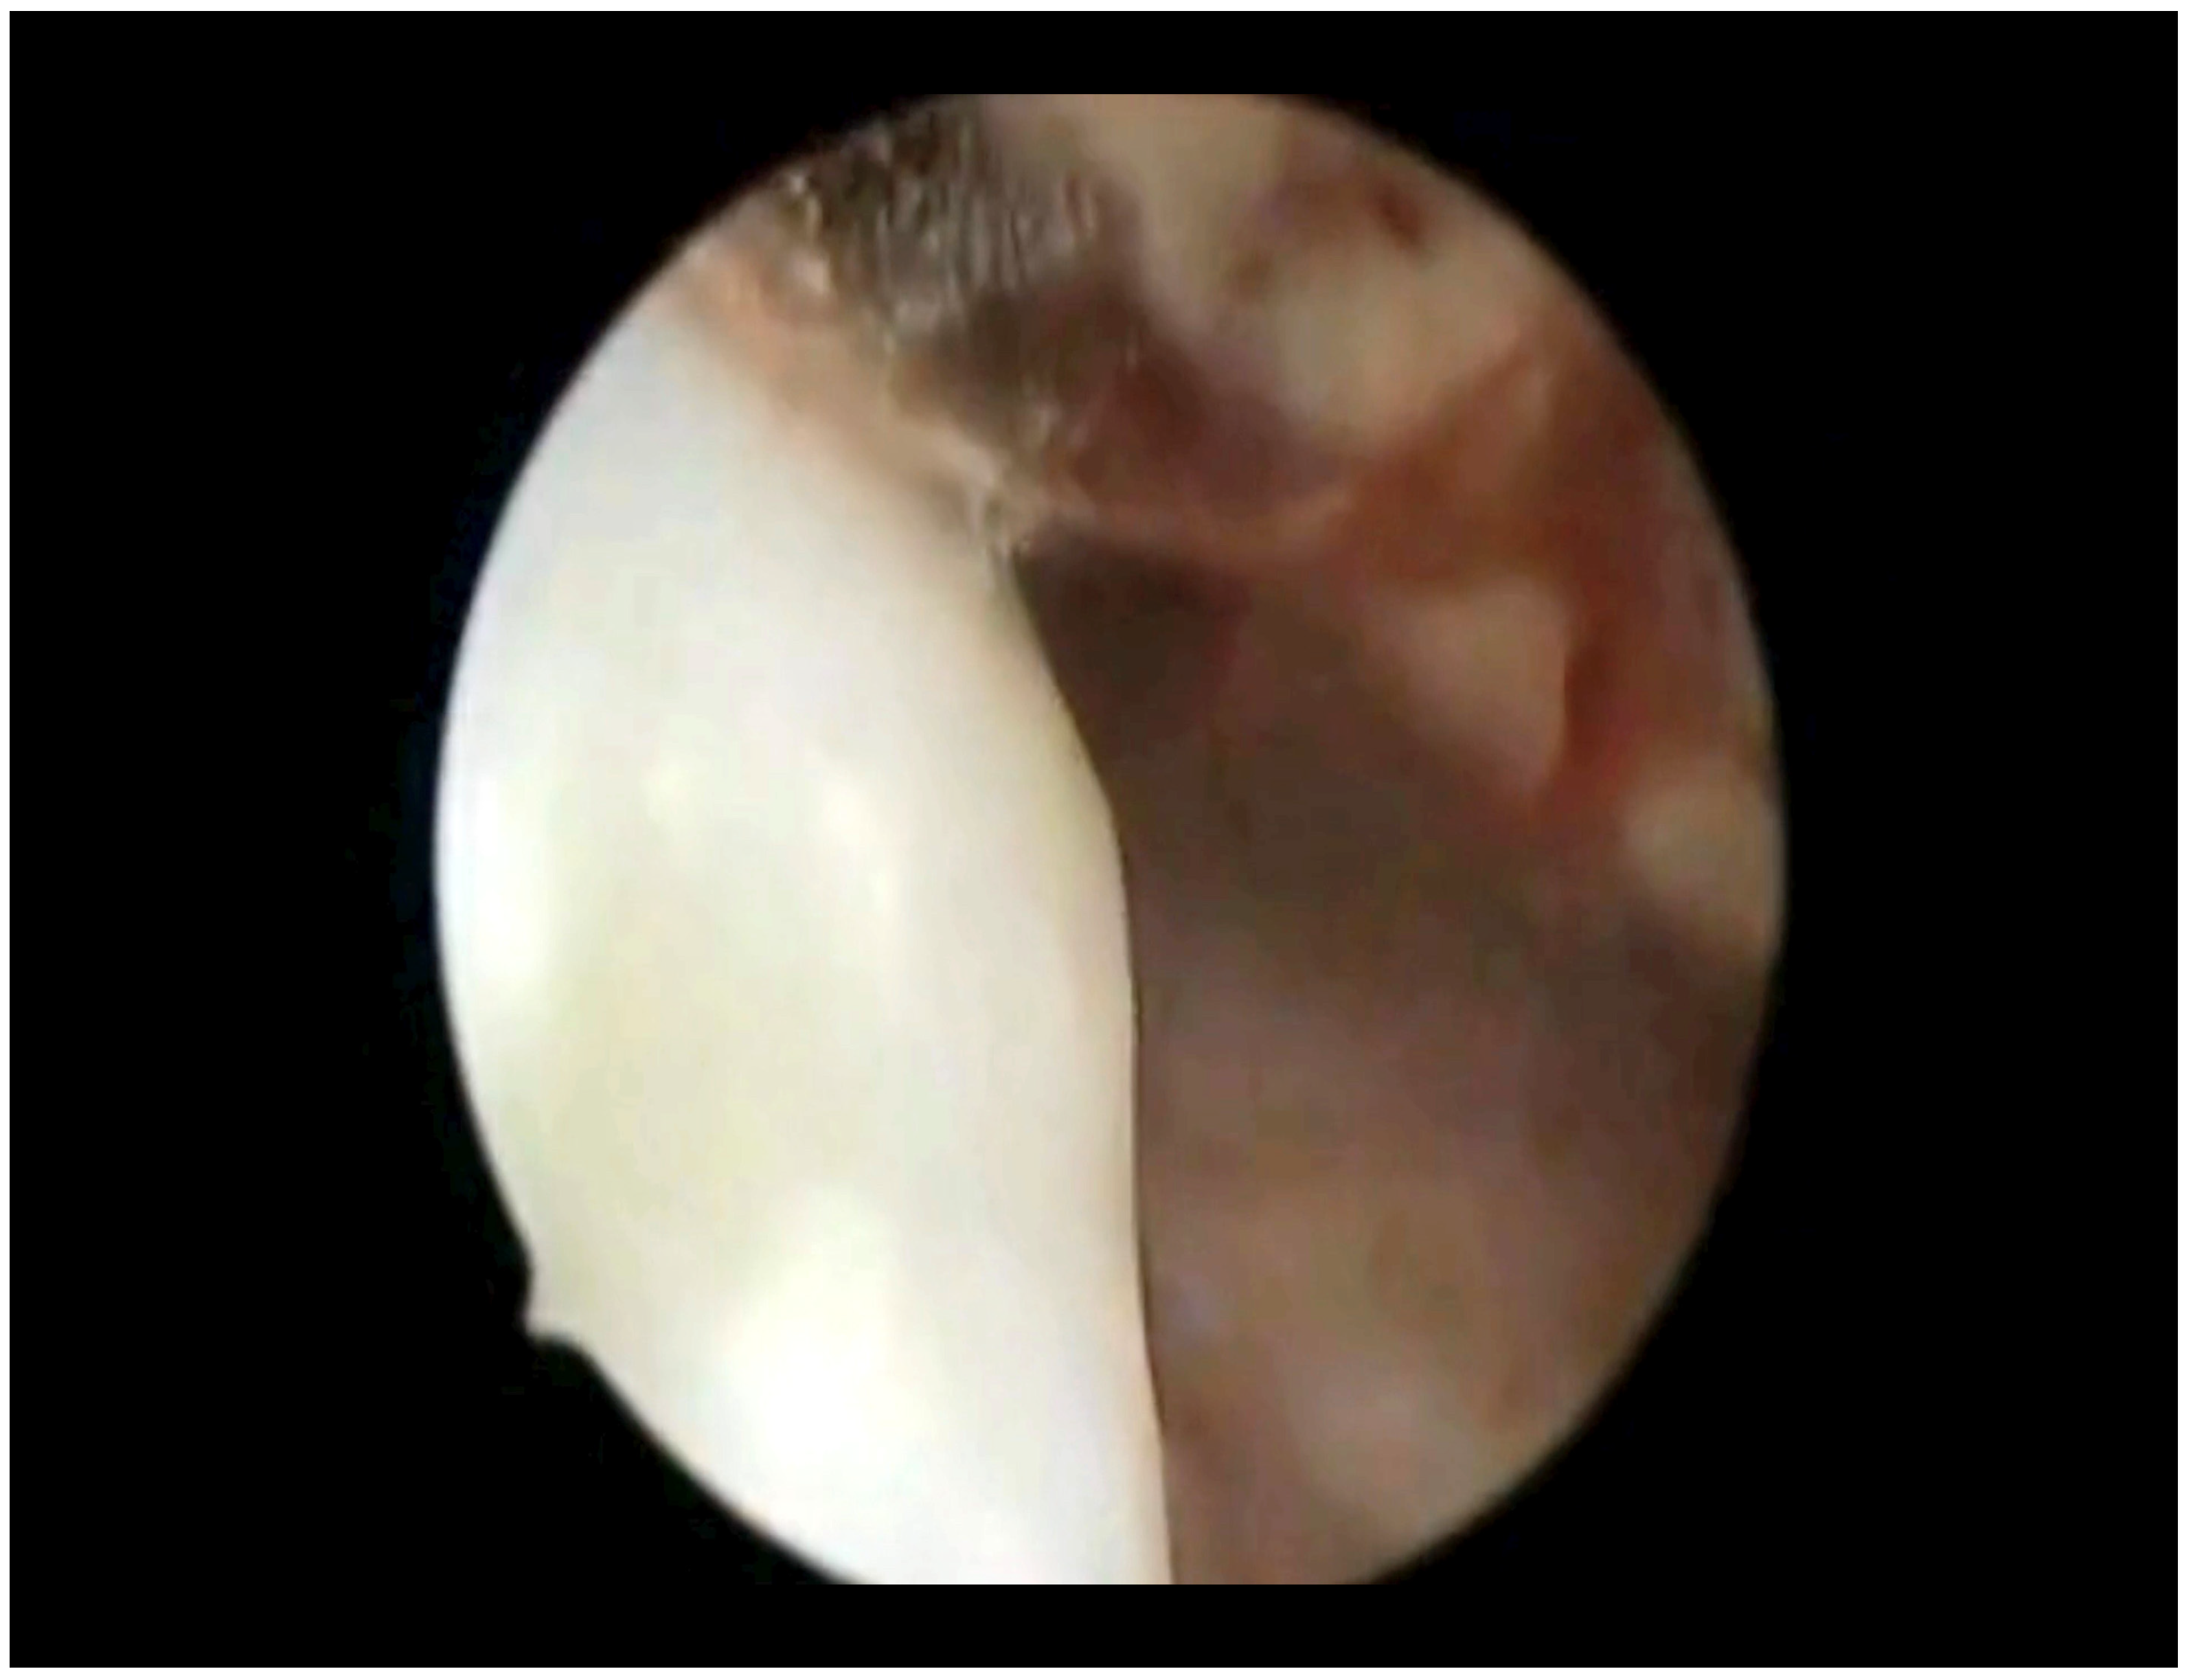

3. Results